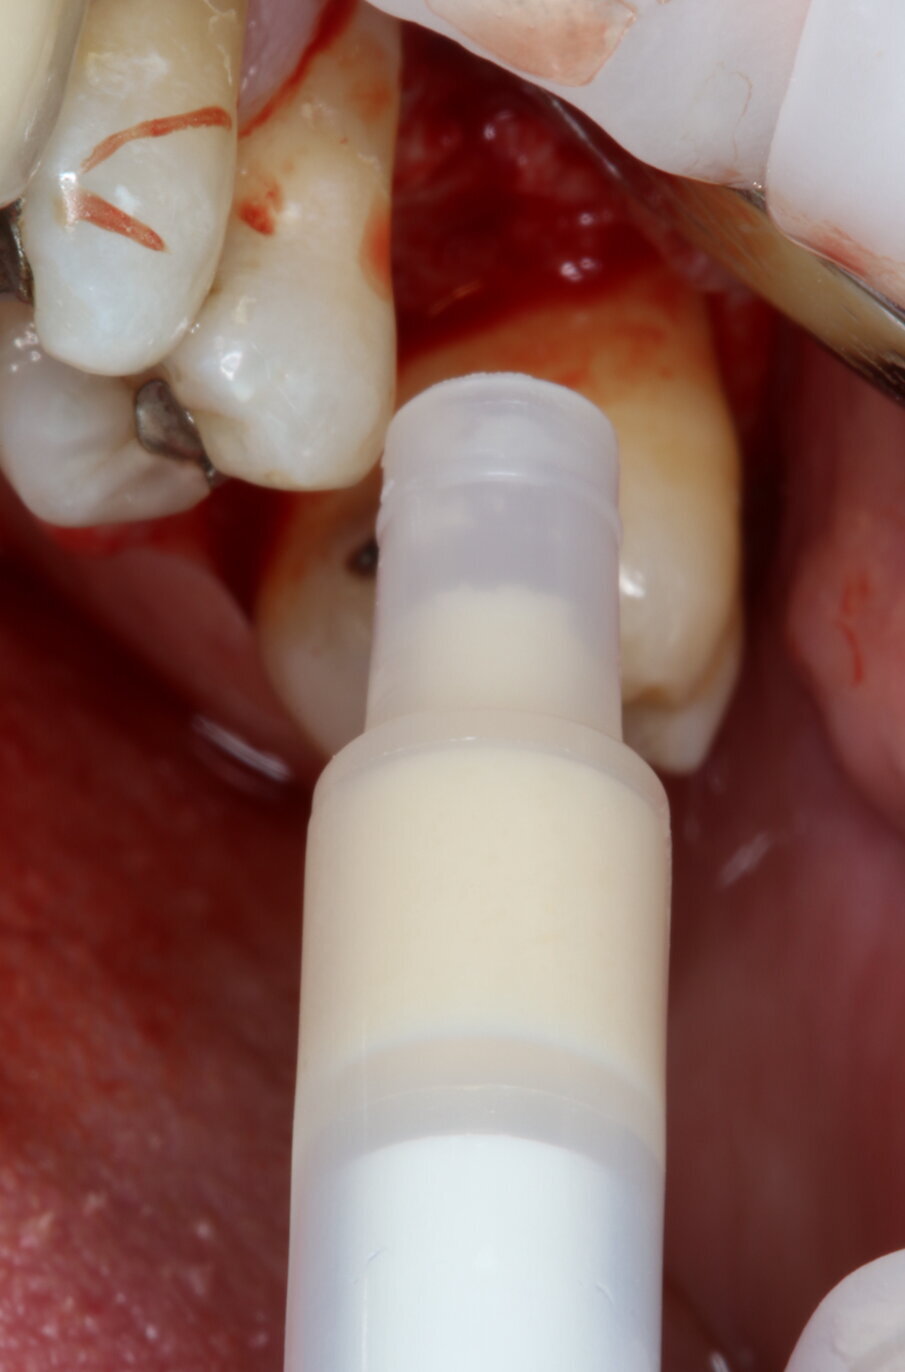

Inserimento del biomateriale

OsteoBiol Putty è stato introdotto con un applicatore dedicato e dosaggio di 0,25 cc, ottenendo un sollevamento uniforme della membrana (Fig. 3).

Fig. 3_Inserimento del biomateriale OsteoBiol Putty.